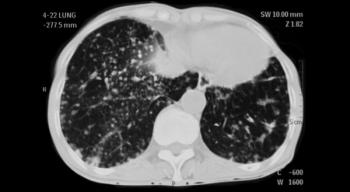

Computed tomography (CT) screening for lung cancer could lead to increased rates of smoking cessation in a high-risk population, with this “teachable moment” extending even to those with negative scan results.

Surgical management of the patient with non–small-cell lung cancer (NSCLC) is complex. When should stereotactic body radiation therapy be used? What are the advantages of video-assisted thoracic surgery? Test your knowledge in our latest quiz.

Proton-beam therapy was found to be safe for patients with limited-stage small-cell lung cancer in the first prospective registry study of the therapy, with only a small number of high-grade toxicities.